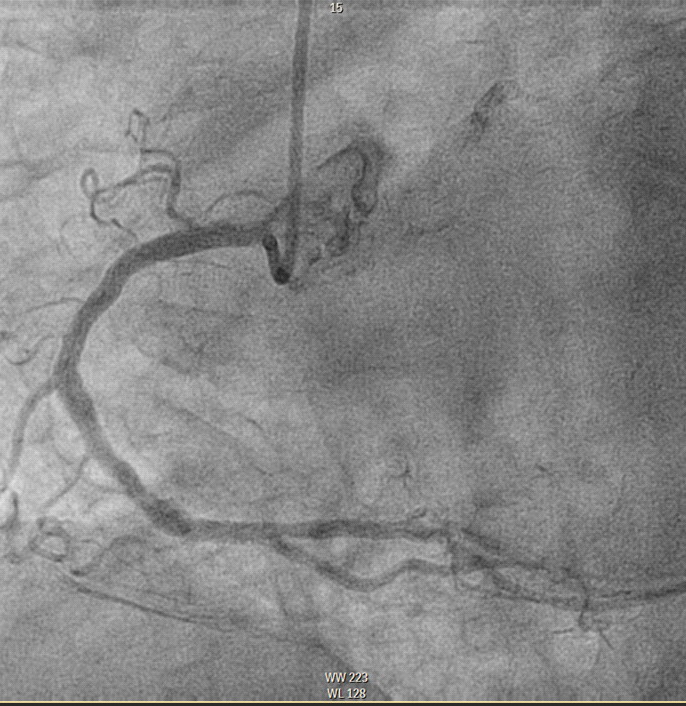

*Coronary angiography: On arrival at the hemodynamics unit, a diagnostic study was performed through the right radial artery in which TIMI 3 flow was observed throughout the coronary tree with no obstructive lesions in the coronary arteries. Good late results of Everolimus-eluting stents previously implanted in the middle LAD, distal LAD and ostial PD. Good result of PTCA on OCT of ostial CX with distal bed of moderate caliber. Moderate lesion at distal CT level (assessed by IVUS). (Figures 3 and 4)

Figure 3 CD without significant lesions.

Figure 4 Moderate injury at the distal CT level.